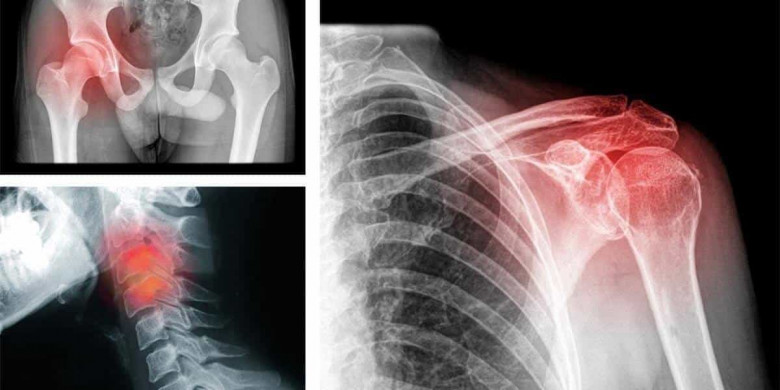

Վզի ցավ

Վզի շրջանում ցավը հաճախ նյարդային սպազմի արդյուն է։ Ցավ ուսերում Սա այն բանի հետեւանք է, որ էմոցիոնալ առումով անչափ լարված ու ծանրաբեռնված եք։ Ցավ մեջքի վերեւի հատվածում

Ցավ ազդրերում